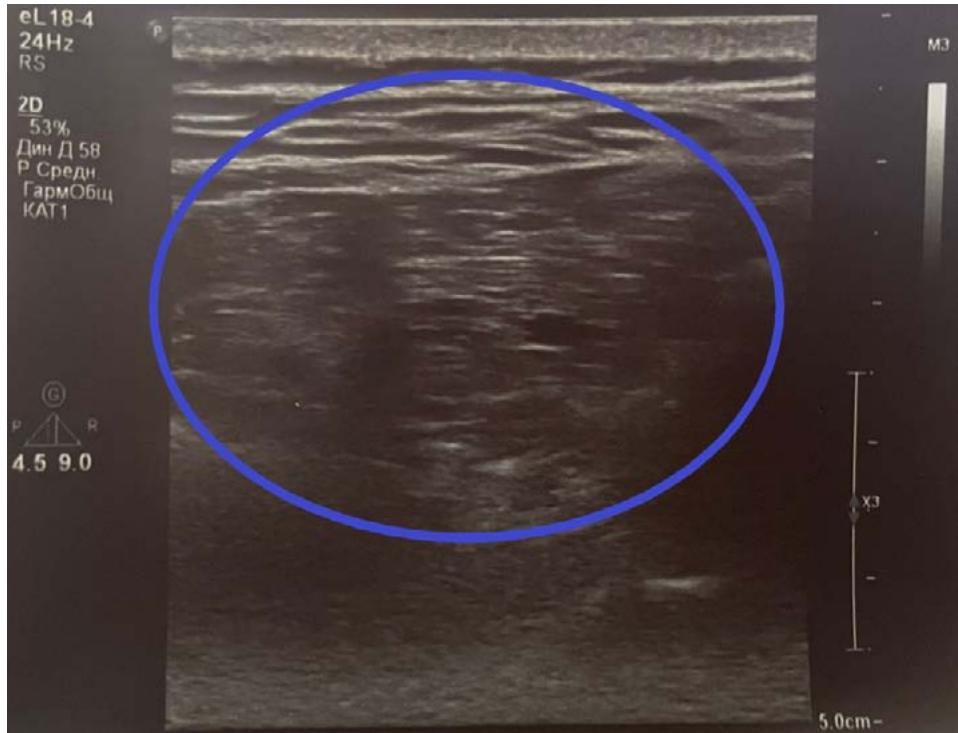

During additional examination, an ultrasound scan (Fig. 7), chest MSCT (Fig. 8) were performed, which showed no evidence for a lipoma, but there was an elastofibroma of the back detected. For differential diagnosis, a biopsy material was taken followed by a histological examination, the obtained results confirmed the diagnosis of "elastofibromadorsi" (Fig. 9).

Figure 6: On examination: a voluminous tumor-like formation along the lower edge of the right scapula. Figure 7: Ultrasound, transverse scan: posterior chest wall: a volumetric mass with an inhomogeneous echostructure is determined.